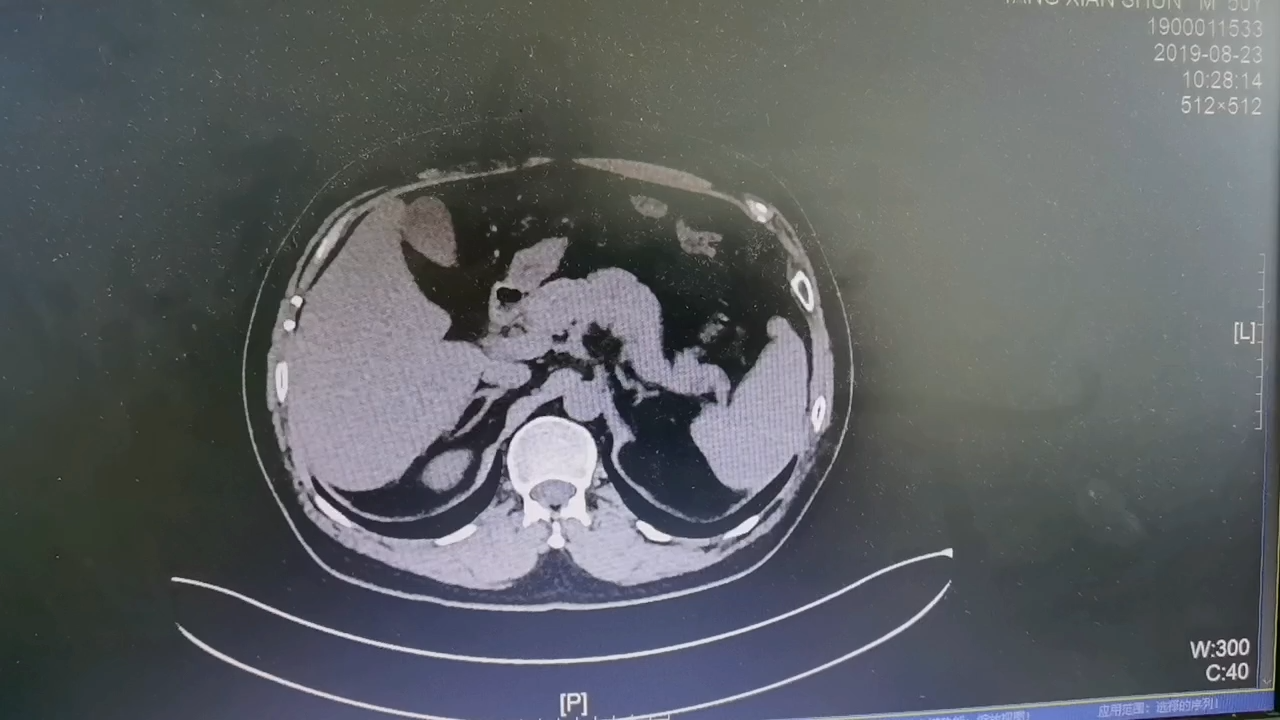

【检查】:CT检查提示右侧腰部切口疝复发。

【临床诊断】:右侧腰部切口疝